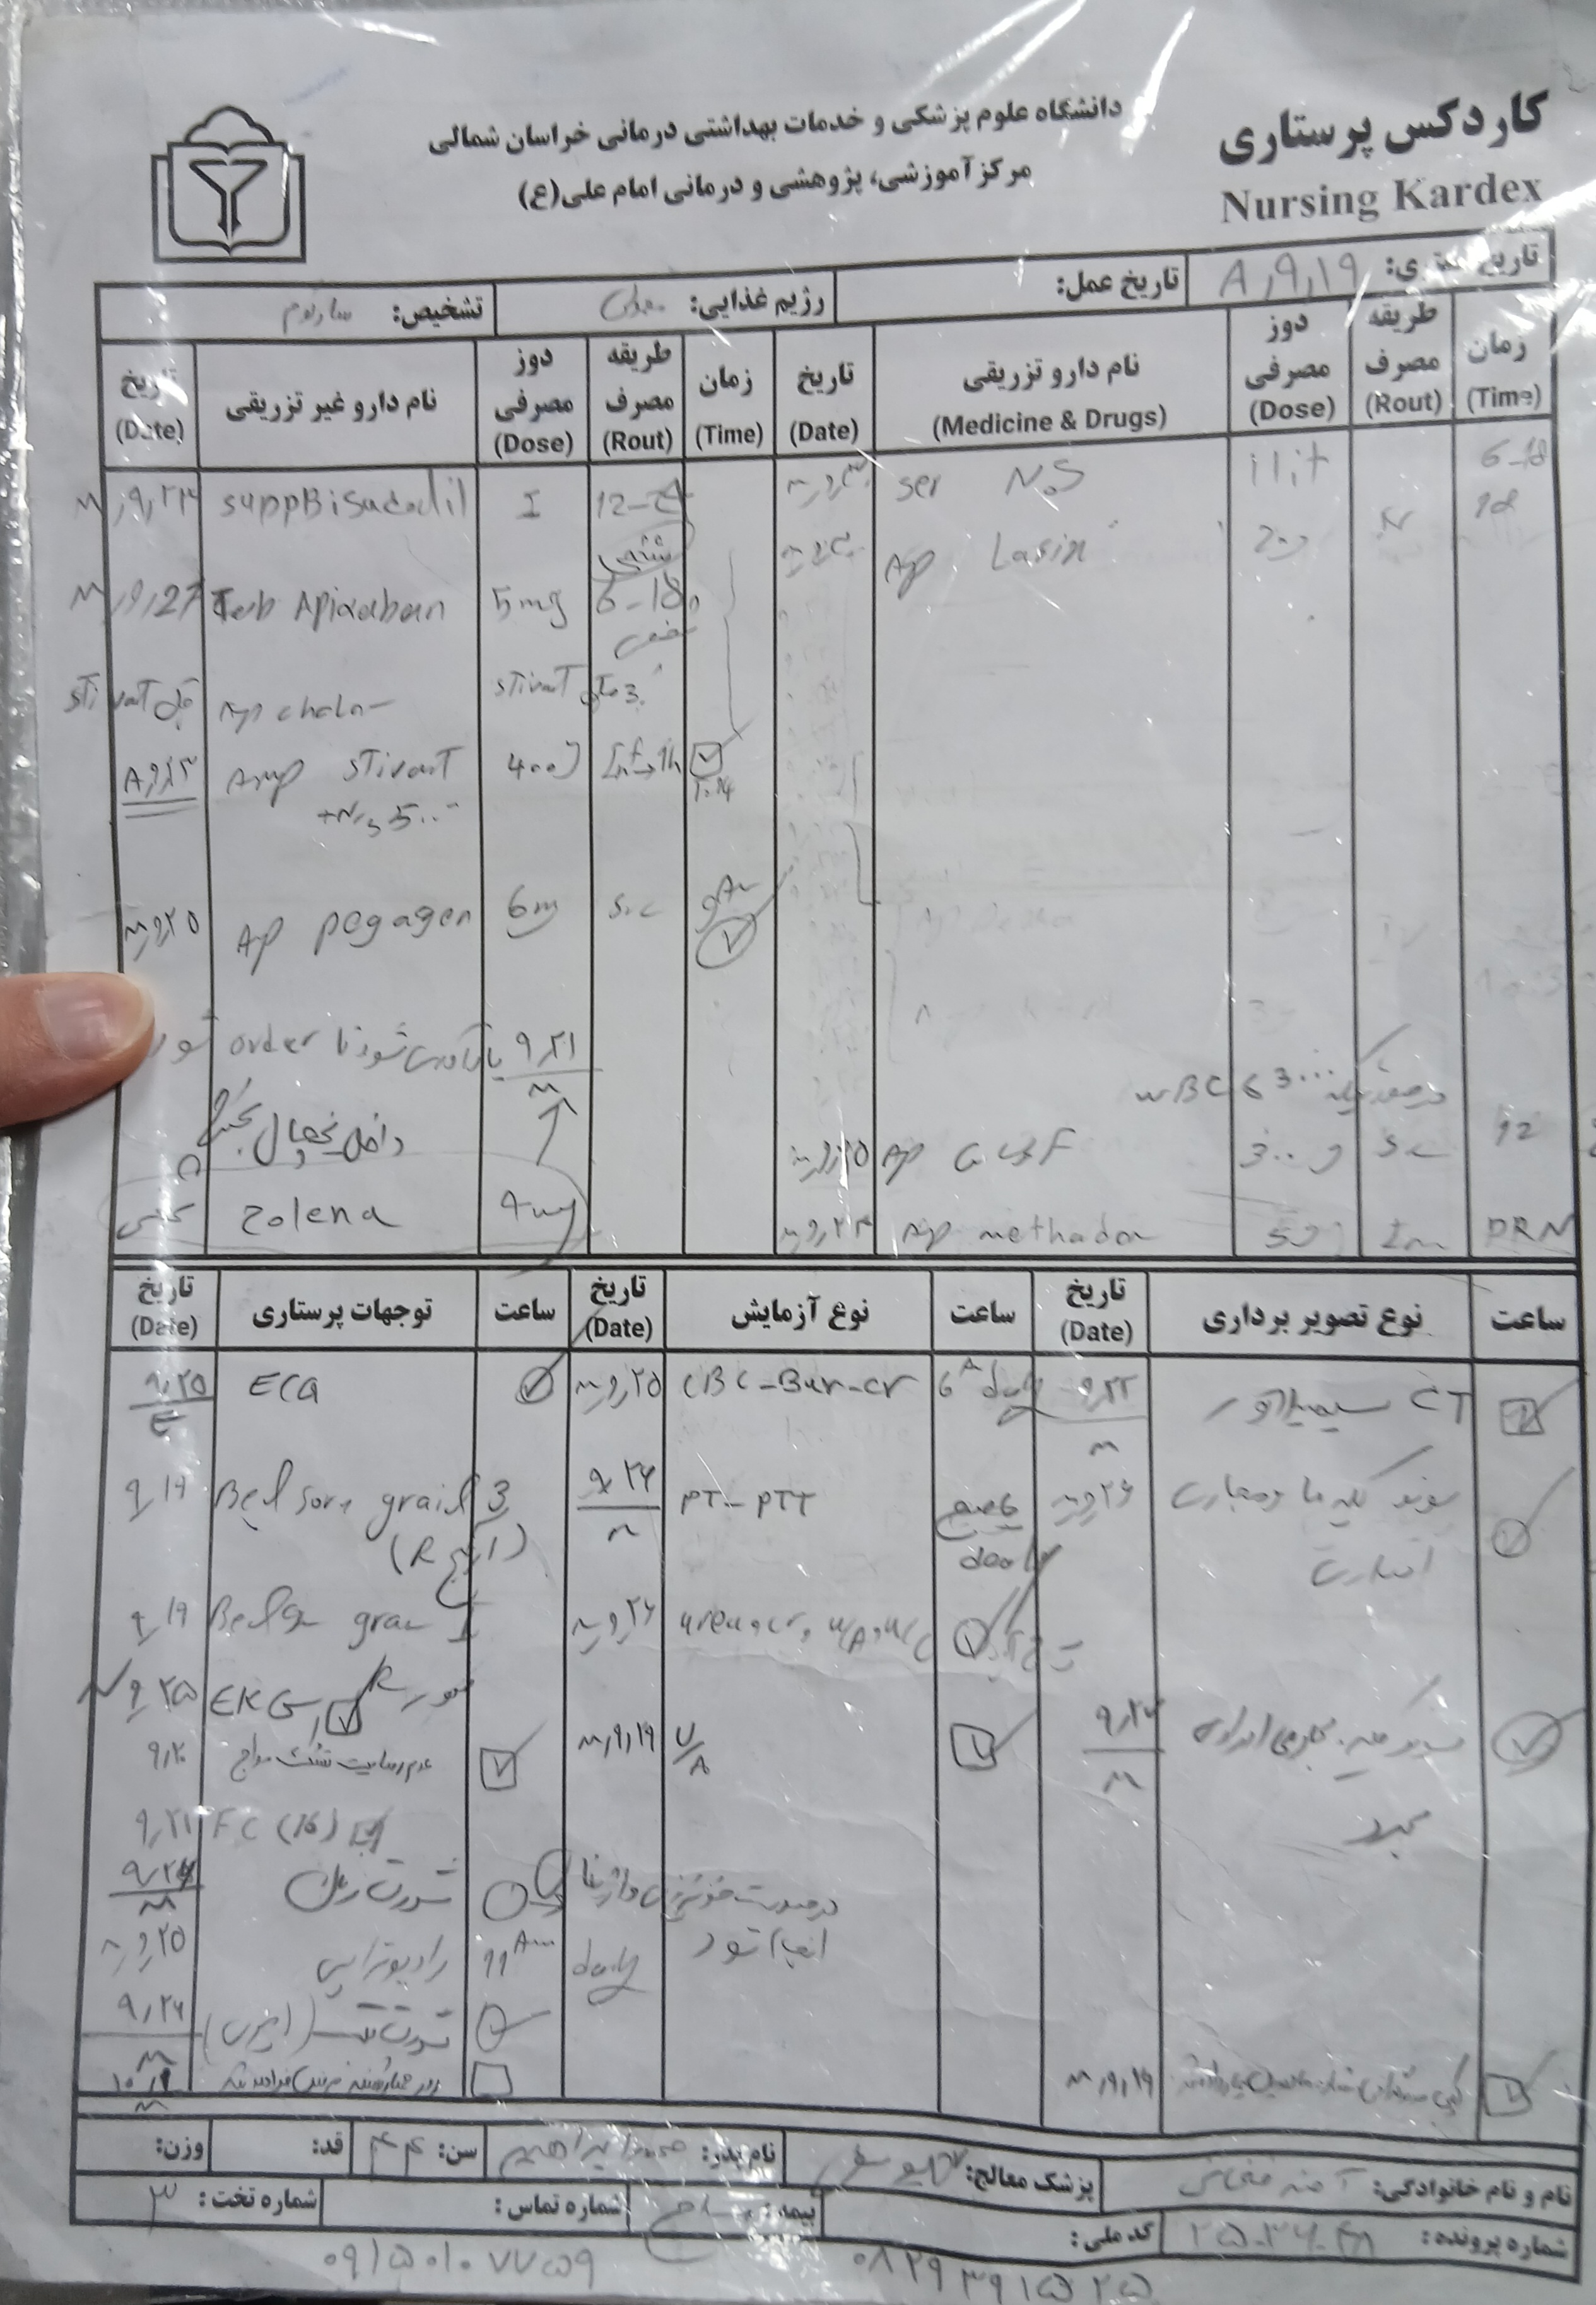

:D.H

Pentomid 40

Valsartan 80

Apixaban 5

Caltonix 200 I.U.

gabapentin 300

(تصویر مربوط به این مراجعه نیست) Other:

(تصویر مربوط به این مراجعه نیست) Other:

(تصویر مربوط به این مراجعه نیست) Other:

(تصویر مربوط به این مراجعه نیست) Other:

به ترتیب؛ روز ها: ۱۹ آبان, ۲۸ آذر, ۲۹ آذر, ۳۰ آذر

به ترتیب؛ روز ها: ۱۹ آبان, ۲۸ آذر, ۲۹ آذر, ۳۰ آذر

۱۹ آذر

۱۹ آذر

به ترتیب؛ روز ها: ۲۸ آذر, ۲۹ آذر, ۳۰ آذر, ۱ دی

۱ دی

Color: Brown

Appearance: Turbid

Protein: Trace

Sugar: Negative

Blood: Positive(++++)

Urobilinogen: Negative

Bilirubin: Negative

Nitrite: Negative

WBC (/HPF): 5-6

RBC (/HPF): Many

Epithelial Cells: 0-1